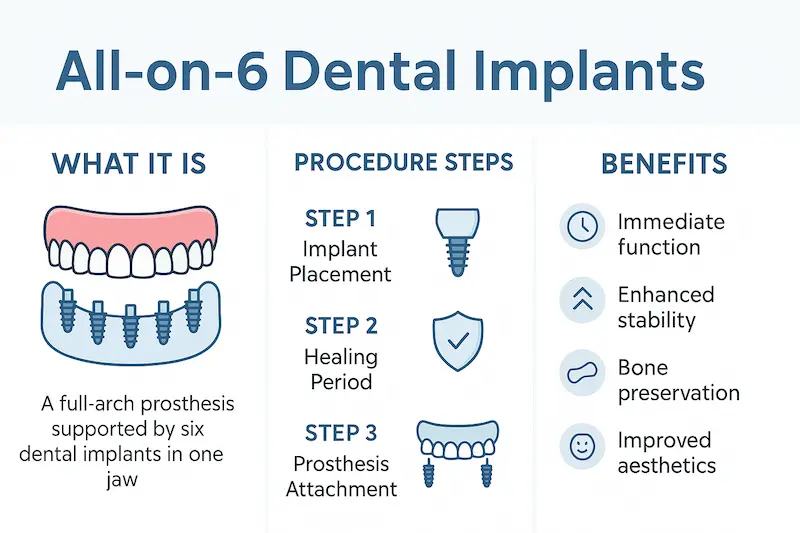

ما هي زراعة الأسنان All on 6؟

تقوم فكرة زراعة الأسنان All on 6 على وضع ستة غرسات (زرعات سنية) في عظم الفك لتحمل طقمًا ثابتًا من الأسنان الصناعية، ما يسمح بتعويض كامل الأسنان المفقودة في الفك العلوي أو السفلي. وتُستخدم هذه التقنية عادةً مع المرضى الذين خسروا غالبية أسنانهم بسبب التسوس الشديد أو الأمراض اللثوية أو الحوادث. يختلف “All on 6” عن بعض الأنواع الأخرى من الأنظمة المشابهة (مثل All on 4) في أنه يستخدم ست زرعات بدلًا من أربع، ما يوفّر:

- ثباتية أكبر وتحمّل لقوى المضغ: إذ تسمح بعض المزروعات الإضافية بتوزيع أفضل للضغط على عظم الفك.

- مرونة في التصميم: قد يتيح هذا النظام خيارات أكثر في تصميم الجسر أو البدلة، خاصةً مع اختلاف أشكال عظم الفك لدى المرضى.

- قابلية أكبر للتعامل مع مشاكل العظم: في بعض الحالات التي لا يلائمها All on 4 بشكل مثالي، يمكن للنظام القائم على 6 زرعات توفير الدعم اللازم من خلال توزيع الغرسات في مواضع مختلفة.

الفوائد الرئيسية لزراعة الأسنان All on 6

- الاستقرار والثبات: إن وجود ست زرعات بدلاً من أربعة فقط يزيد من قوة التحمل وتحسين توزيع الحمل على الفك، وبالتالي يزيد من عمر الجسر الصناعي ويمكّن المريض من مضغ الطعام بارتياح أشبه بالأسنان الطبيعية.